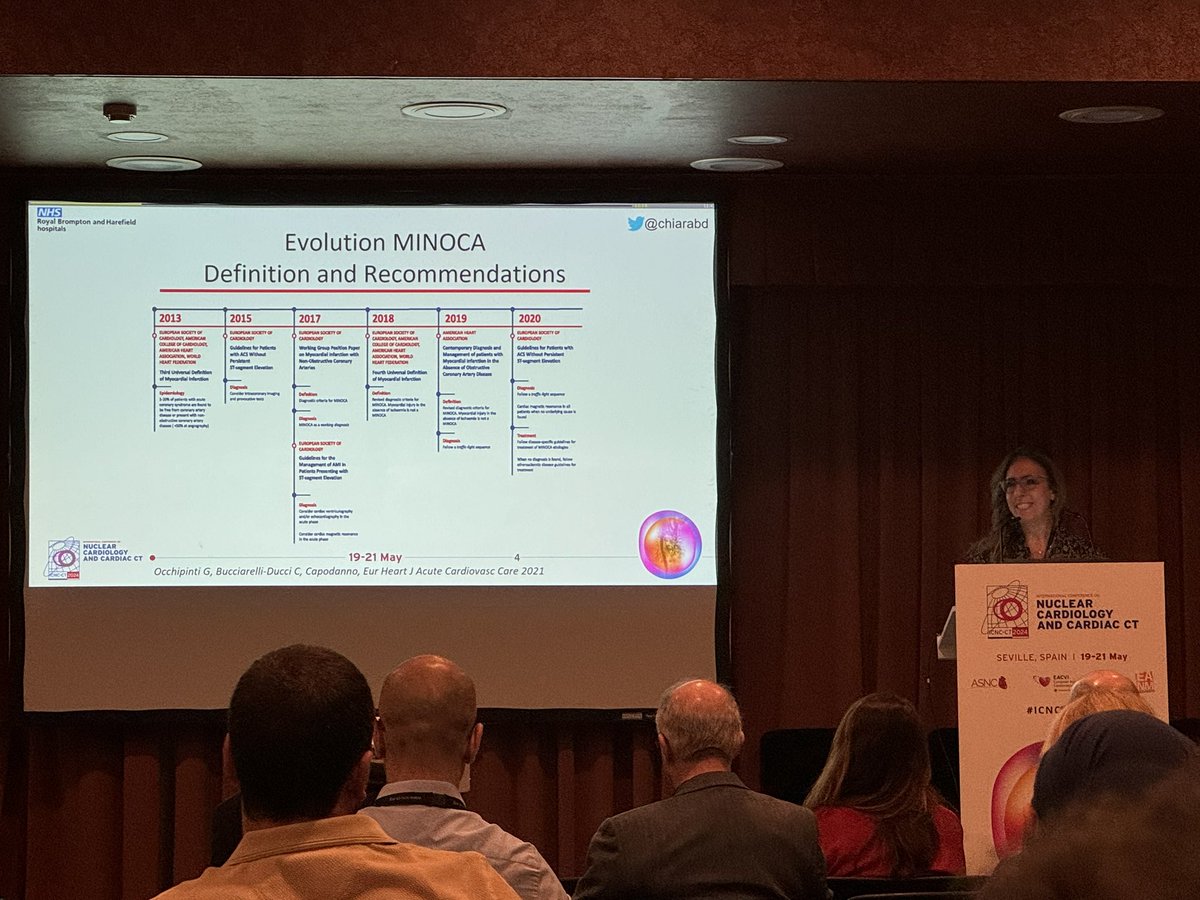

Great pleasure to listen to the fantastic C Bucciarelli-Ducci talking about MINOCA #ICNCCT2024

#ICNCCT2024 #CMR reclassifies diagnosis of MINOCA C Bucciarelli-Ducci shows the value of the modality